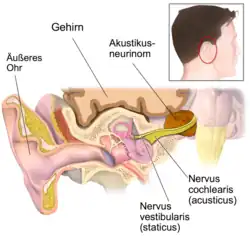

Ein Akustikusneurinom (kurz AKN oder AN) ist ein gutartiger Tumor, der von den Schwann’schen Zellen des vestibulären Anteils des VIII. Hirnnerven, des Hör- und Gleichgewichtsnerven (Nervus vestibulocochlearis), ausgeht und im inneren Gehörgang, bei größerer Ausdehnung auch im Kleinhirnbrückenwinkel gelegen ist. Das Akustikusneurinom ist histologisch eigentlich als Vestibularis-Schwannom zu bezeichnen. Die Bezeichnung Akustikusneurinom ist aber klinisch üblich.[1] Es ist der häufigste Kleinhirnbrückenwinkeltumor.

Dabei fällt meist zuerst eine einseitige Hörstörung vor allem für hohe Töne auf, z. B. beim Telefonieren. Der Schwindel ist meist unsystematisch, kein Drehschwindel wie bei einer Störung des Gleichgewichtsorgans. Auch entstehen die Symptome langsam. Mit Messgeräten ist dagegen zuerst die Gleichgewichtskomponente nachweisbar, da das AKN ja eigentlich nicht vom akustischen Anteil (N. cochlearis), sondern vom Gleichgewichtsanteil (N. vestibularis) des N. vestibulocochlearis ausgeht.